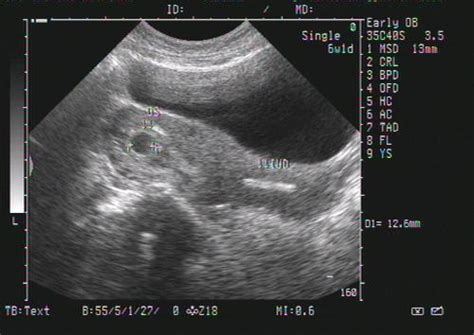

怀孕8个月的B超数据

根据孕周表,您的宝宝双顶径和骨长,也就是头部横径和大腿骨长都发育正常,胎心和羊水深度也在范围值内,脐带血阻比也正常。

不必担心,更不用提前剖腹产,完全可以顺产的。

怀孕8个月胎儿B超数据

怀孕八个月B超结果如下:双顶径80mm.胎心率132次/分,股骨长59mm,羊水深约61mm,内透声好。胎盘附于子宫前壁,厚约28mm,绒毛板轻度起伏。这样正常吗,知不知道有几斤?谢谢

2000克左右!

31周左右,一切正常!